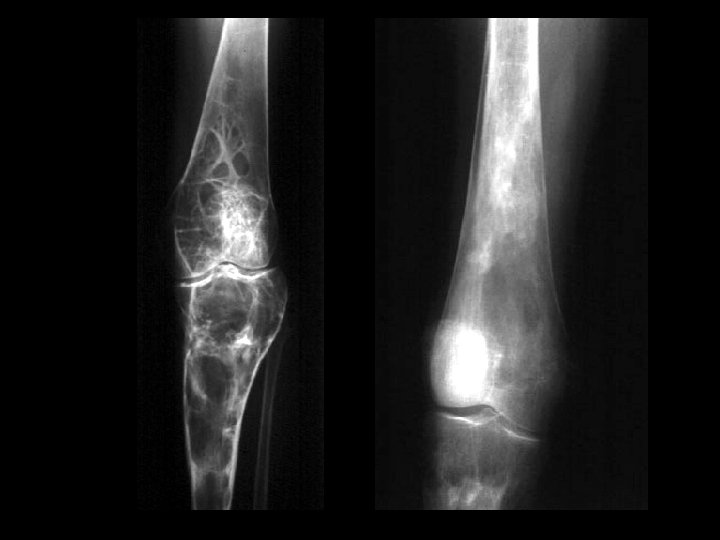

Hemangioma • Findings: – expansile lesion of the proximal tibia containing fine bony septations and a large course calcification – CT scan shows a lacey appearance • ddx: – Paget’s dz – ABC